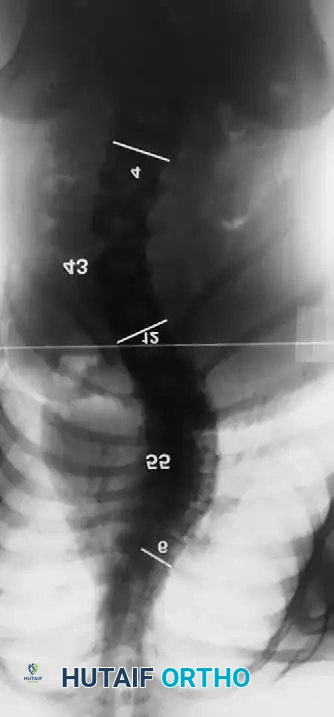

Associated Surgical & Radiographic Imaging